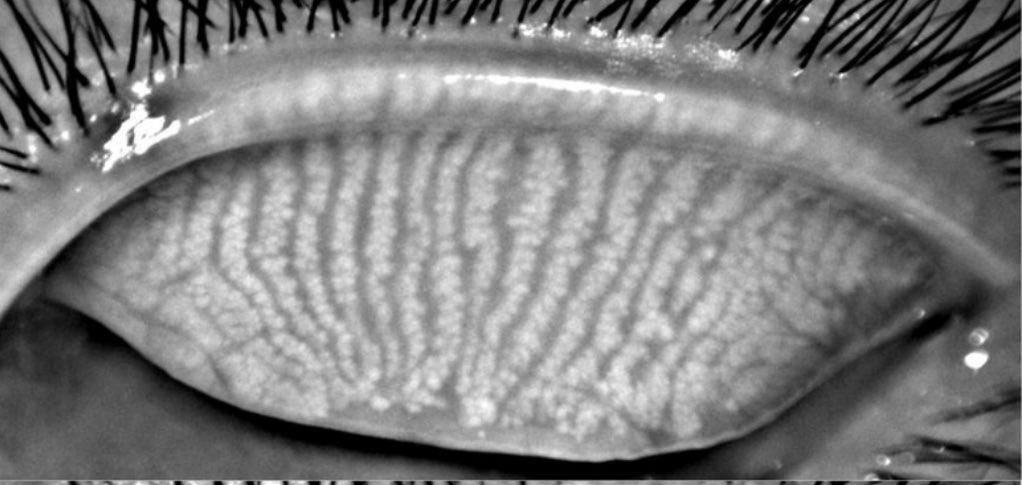

الصورة المرفقة تبين قنوات الغدد المفرزه للمادة الزيتية التي تساعد في تكون الدمع وتحافظ على جودته وتسمى بغدد ميبوميان !!

غدد ميبوميان هي غدد دهنية دقيقة تبطن حواف جفون العين (الحواف التي تتلامس عند إغلاق الجفون)، عددها تقريبا 50 في الجفن العلوي وحوالي 25 في السفلي !

تفرز هذه الغدد المادة الزيتية الذي تغطي سطح العين وتحافظ على المكون المائي للدنع لدموعنا من التبخر (الجفاف)!

وهذي الماده الزيتية تعتبر مكون اساسي في الشريط الدمعي لولاها لأصبحت اعيننا جافة في ثواني !!

اختلال عمل غدد ميوبوميان نتيجة بعض الامراض يسبب تشوه في شكلها او نقص في عددها ويصاحب هالشي تعطل افرازها لهذي الماده الزيتية او تفرزها بجودة سيئة وراح تسبب عدة مضاعفات منها جفاف وعدم وضوح الرؤية و تهيج العين واحمرارها وزيادة نسبة تعرضها للالتهابات !!

ايضا في كثير من الاحيان ممكن تتعرض فتحات هذي الغدد للانسداد ، نتيجة التهاب الجفون مثلا وفي هذي الحاله الماده الزيتيه الي تفرز من الغدد تكون حبيبية وجافة وقشرية وتراكمها على الجفون يكون غير طبيعي ، ويمكن يسبب التهاب وتشكل حبوب الجفن .